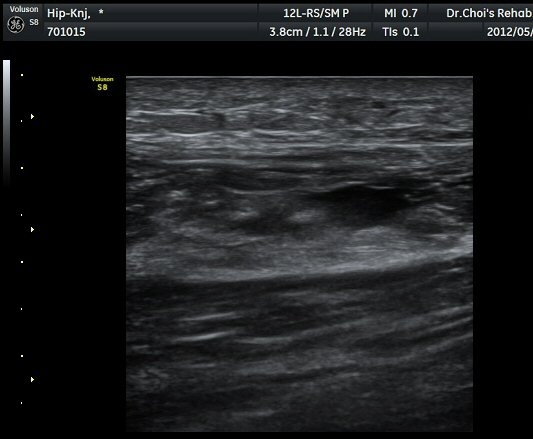

ÀüÇÏÀå°ñ±Ø(AIIS) Ⱦ´Ü¸é °Ë»ç»ó ÀüÇÏÀå°ñ±Ø°ú µÇÅðÁ÷±ÙÀÇ ÈûÁÙÀÌ °üÂûµÈ´Ù(±×¸² 1).